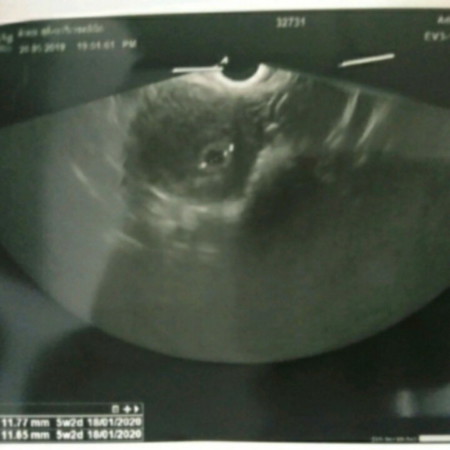

สวัสดีค่ะพอดีแม่เป็นสมาชิกใหม่อยากขอคำแนะนำจากแม่ๆ พอดีไปฝากท้องมาวันที่20 พค. 5w2d หมอบอกว่าเห็นแต่ถุงตั้งครรภ์แต่ไม่เห็นตัวอ่อน แม่อยากทราบว่าปกติอายุครรภ์ประมาณนี้ควรจะเห็นแล้วหรือยังน้อยอยู่คะ แม่กลัวท้องลมเหมือนที่หมอบอกค่ะ ขอคำแนะนำด้วยนะคะ ขอบคุณค่ะ

อย่าเพิ่งกังวลนะคะแม่ เราซาวตอน 6w+6d ก็เห็นแต่ถุงตั้งครรภ์คะ หมอนัดซาวตอน8wก็เห็นตัวน้องคะ ตอนแรกแอบกังวลเหมือนกันคะกลัวท้องลม อย่าเพิ่งเครียดนะคะ

ของเราซาวตอน5w+3 เจอแต่ถุงตั้งครรภ์ หมอนัดซาววันฟังผลเลือดอีกรอบ อายุครรภ์6w+2เจอตัวน้องค่ะ แต่เล็กมาก แม่อย่าเครียดนะคะ เดี๋ยวก็เจอน้องค่ะ

ของเรา 5W 6D ก็เห็นแต่ถุงค่ะ หมอบอกว่าอายุครรภ์ยังน้อย จะเห็นชัดมากๆตอน 8W คุณหมอนัดไปตอน 8W เลย รอลุ้นค่ะ ว่าจะเห็นน้องมั้ย อย่าเพิ่งกังวลนะคะ

ซาวเมื่อตอน6w1d เจอถุงตั้งครรภ์แต่ไม่เจอเด็ก หมอนัดอีกทีวันที่17นี้ค่ะ หมอบอกว่าคุณแม่มีโอกาสท้องลมเพราะอายุ39แล้ว พยายามไม่เครียดค่ะ